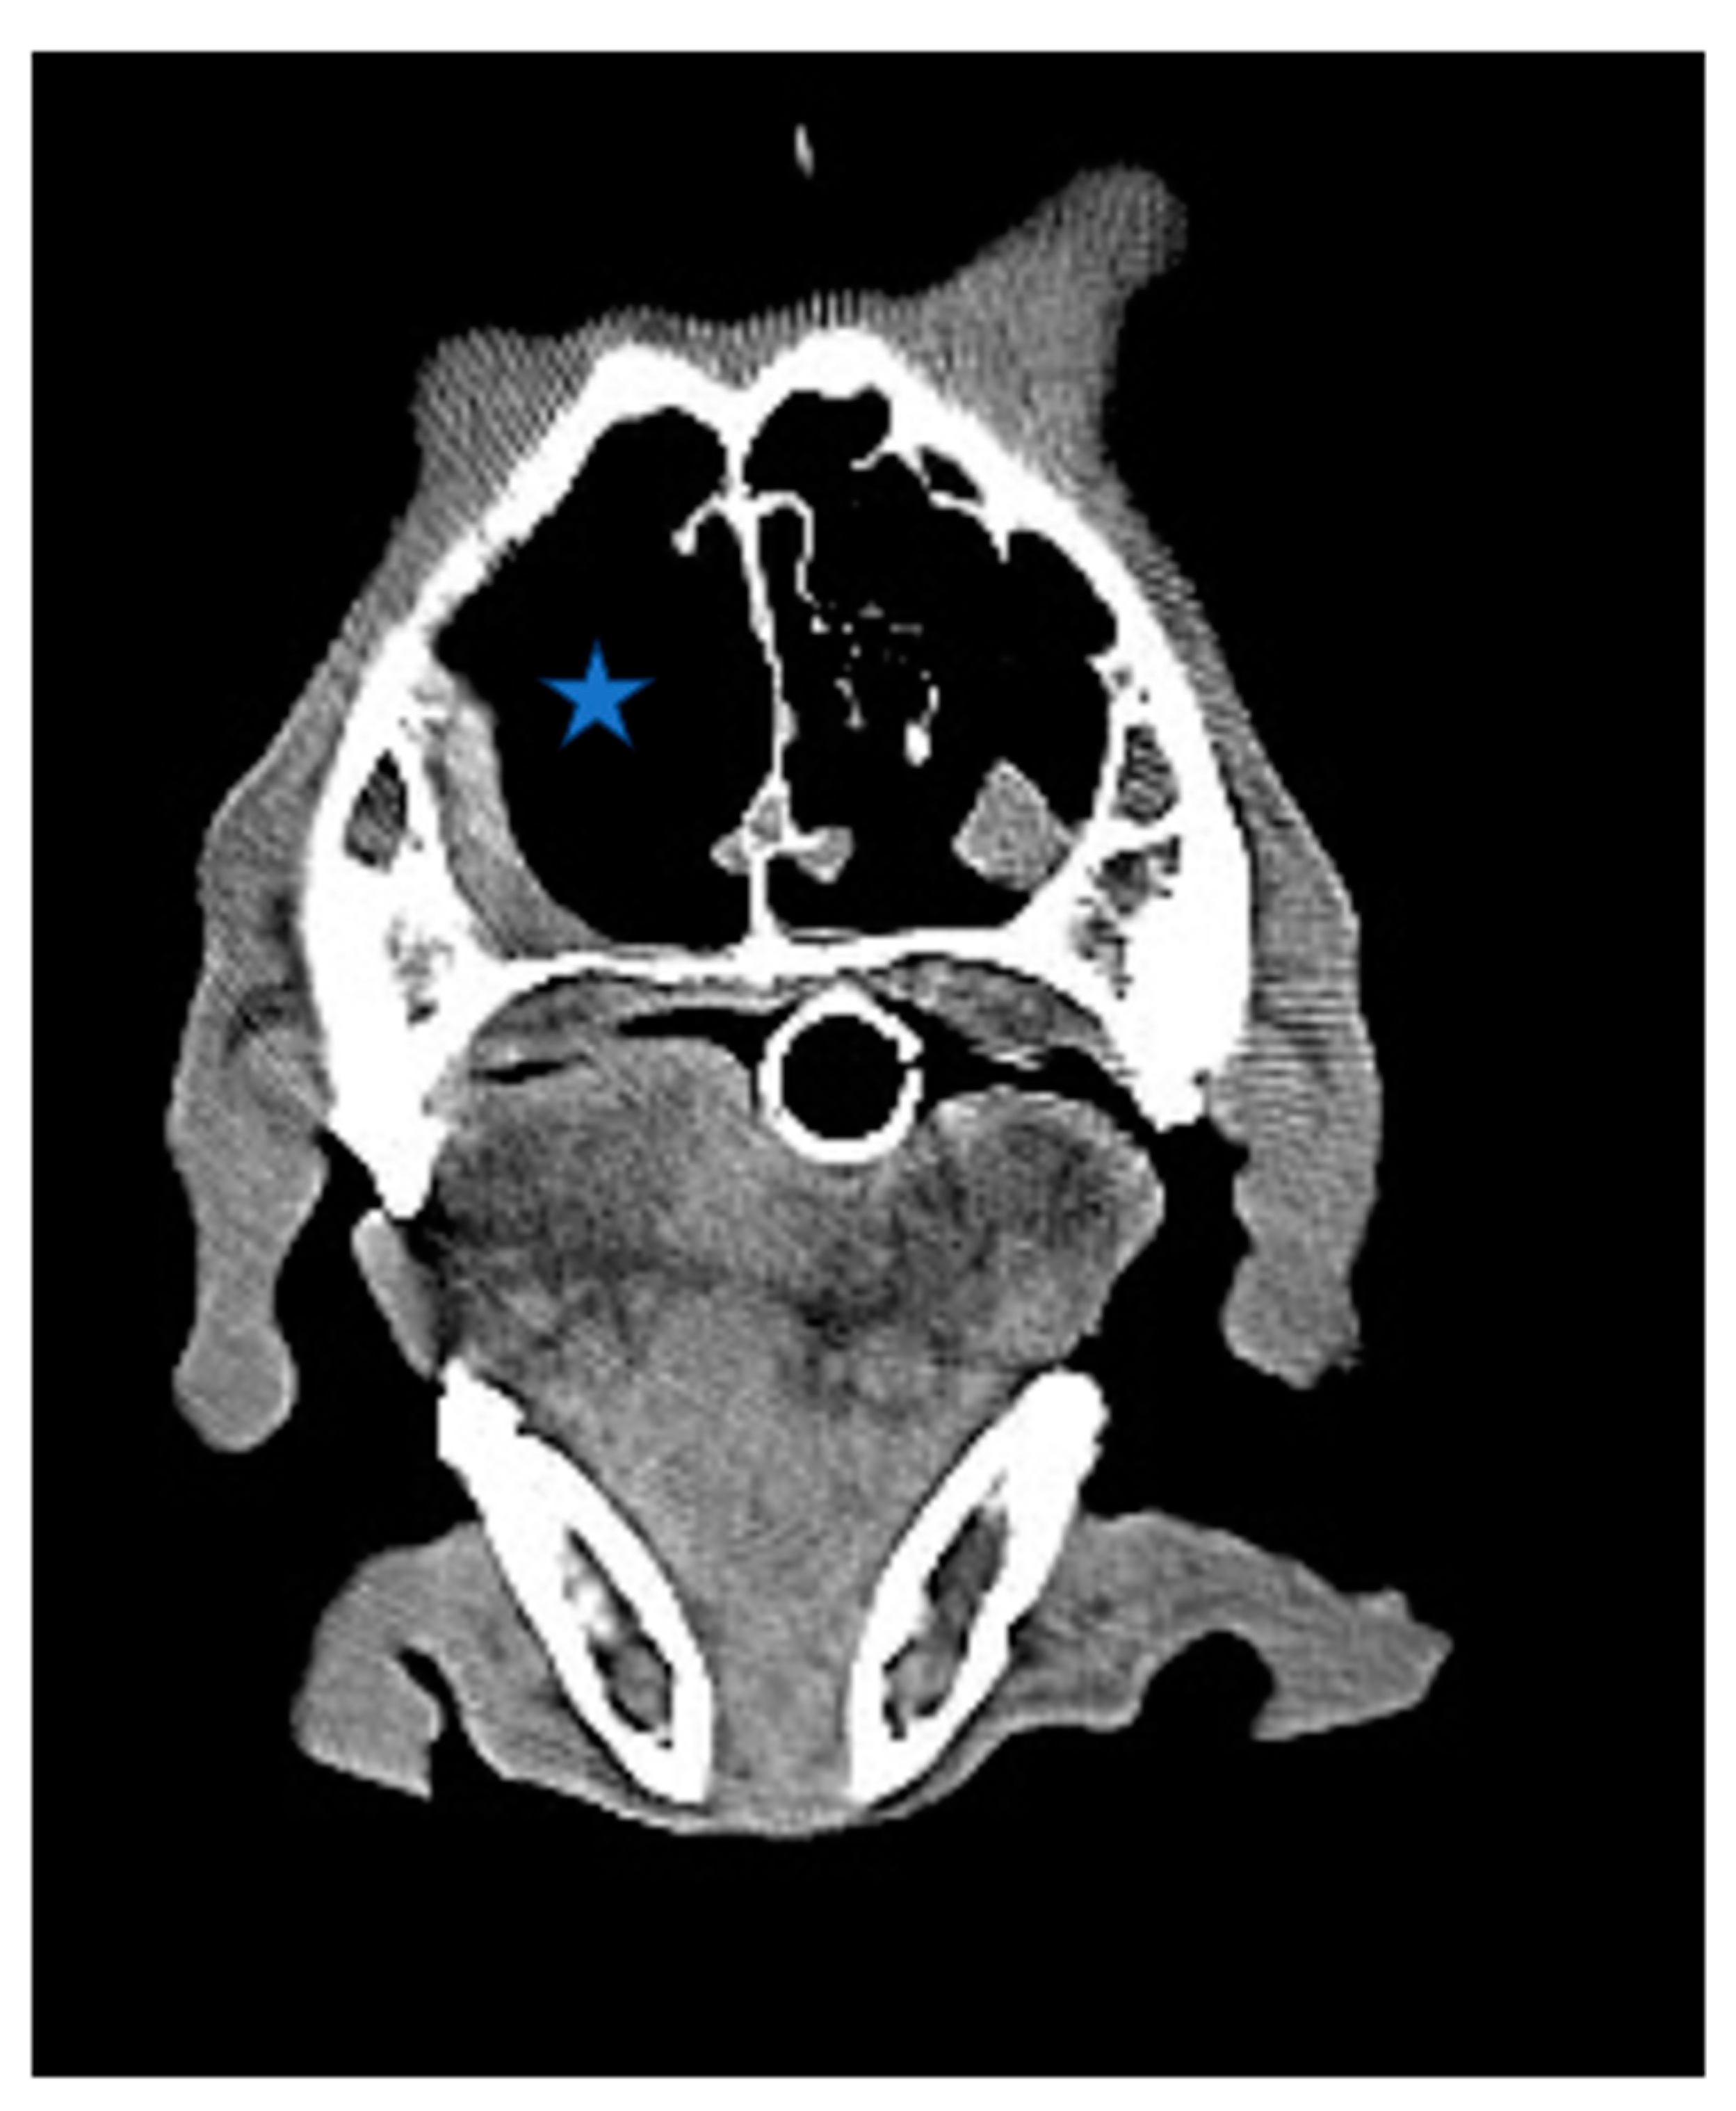

Figure 2. (A,B,C). Axial view of CT scan of skull. The size of the tumor decreased significantly after radiation/chemotherapy compared with before radiation/chemotherapy, after radiation, and before chemotherapy (Asteroid).